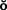

Today the continued high rate of success achieved with osseous integrated dental implants allows a greater number of patients to enjoy the benefits of fixed rather than removable dental prostheses.1-3 The main indications for implant-supported restorations in the partially edentulous patient are the free-end distal extension, in which no posterior abutment is available (Fig. 13-1), and the long edentulous span. In both these situations, the conventional dental treatment plan would include a partial removable dental prosthesis. However, with the advent of dental implants, the patient can benefit from fixed restorations. In addition, in the short edentulous span, the single dental implant is a popular option (Fig. 13-2).

Fig. 13-1 Implant-supported fixed prosthesis. Four dental implants (A) supporting a fixed dental prosthesis (B).

Fig. 13-2 A, Single-tooth implant with an internal anti-rotational feature. B, Implant crown replacing a single missing tooth (cement retained).